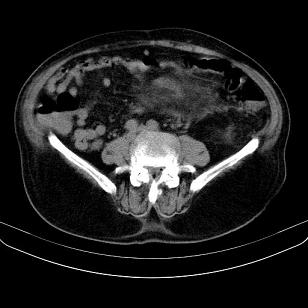

标题: CT21671:男,88岁,左上腹包块 [打印本页]

标题: CT21671:男,88岁,左上腹包块

患者因咳嗽而住院,自觉右上腹包块,无其他不适。

支持;后腹膜脂肪肉瘤诊断。

另肠腔扩张及液平,肠梗阻?